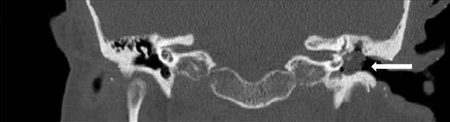

- Tomografia computadorizada (TC) dos ossos temporais petrosos:

opacificação da orelha média, erosão ossicular e erosão do scutum; pode demonstrar envolvimento intracraniano, coclear, da mastoide ou do canal semicircular